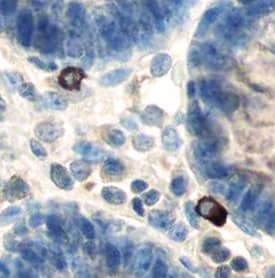

HGF Receptor/c-MET in Human Colon.

Hepatocyte Growth Factor Receptor (HGF R)/c-MET) was detected in immersion fixed paraffin-embedded sections of human colon using Human HGF R Monoclonal Antibody (Catalog # MAB3583) at 15 µg/mL overnight at 4 °C. Tissue was stained using the Anti-Mouse HRP-DAB Cell & Tissue Staining Kit (brown; Catalog # CTS002) and counterstained with hematoxylin (blue). View our protocol for Chromogenic IHC Staining of Paraffin-embedded Tissue Sections.

This antibody specifically recognizes human HGF R. Reactivity with HGF R from other species has not been determined.